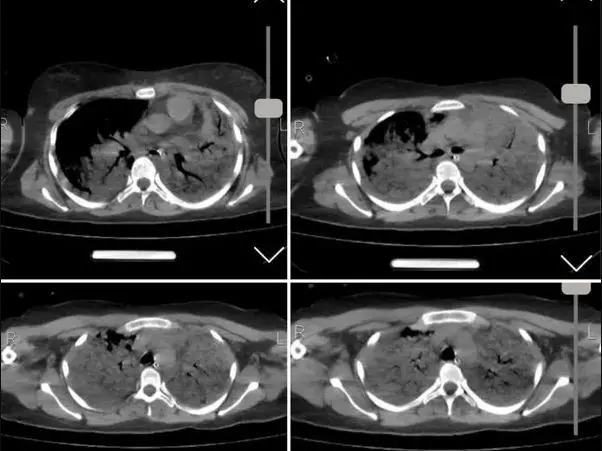

خبرگزاری فارس نوشت:صبح امروز شبکه اینترنشنال وابسته به عربستان سعودی عکسی از سی‌تی اسکن مرحوم مهسا امینی منتشر کرد و مدعی شد که «سی‌تی اسکن مهسا نشانگر شکستگی جمجمه، خون‌ریزی و ادم مغزی است».

با اینکه در ابتدا تصور می شد این تصاویر به مانند بسیاری از اخبار این رسانه سعودی جعلی باشد اما پیگیری های خبرنگار فارس از مراجع ذیربط نشان داد تصاویر سیتی اسکن منتشر شده مربوط به مرحوم مهسا امینی است.

بنابر گزارش دیده بان ایران؛ ارگان رسانه ای نزدیک به سپاه ادعا کرد: برای بررسی علمی این موضوع با تعدادی از پزشکان مغز و اعصاب و رادیولوژیست گفت‌وگو کردیم تا به صورت علمی این موضوع را بررسی کنیم. این متخصصان معتقدند بررسی‌های سی تی اسکن بیمارستان نشان می‌دهد هیچ شواهدی از ضربه به سر و خونریزی در این تصاویر به چشم نمی‌خورد.  یک متخصص جراحی مغز و اعصاب به خبرنگار ما گفت: بررسی‌ها نشان می‌دهد که بیمار در گذشته جراحی در ناحیه سر انجام داده است اما براساس شواهد موجود از روی سی‌تی‌اسکن نمی‌توان فهمید که جراحی دقیقاً مربوط به چند سال قبل است.همچنین شواهد کرانیتومی فرونتوتمپورال قبلی همراه با آتروفی مختصر عضلانی و تغییرات بافت نرم در محل جراحی بیمار مشهود است.

فارس همچنین مدعی شد: یکی دیگر از پزشکان مغز و اعصاب نیز جراحی تومور بیمار را تایید می‌کند. به گفته این متخصص مغز و اعصاب متاسفانه برخی از افراد با دیدن تصاویر ناقص سی تی اسکن درفضای مجازی اقدام به اعلام نظر کرده‌اند اما واقعیت این است که در تصاویر کامل اثری از شکستگی نیست و این رسانه سعودی تصاویر را از زاویه‌ای منتشر کرده است که شکستگی به نظر برسد.